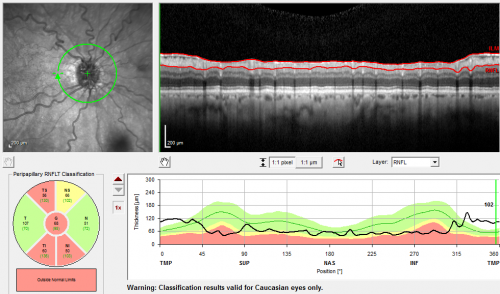

Optic Nerve Drusen - - Nerve Fiber Layer Scan

72-year-old woman has had optic nerve drusen for sometime and has visual field abnormalities. OD 20/32, OS 20/32.